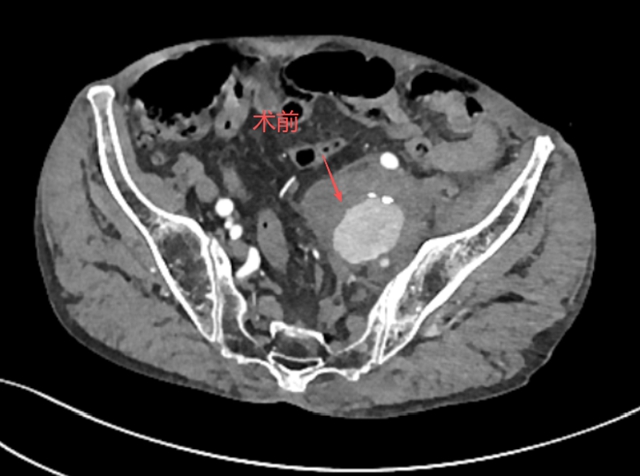

张大爷以为休息一下会好转,但疼痛不仅没有减轻,反而逐渐加重。家人见他面色苍白、满头冷汗,立即将他送往当地医院。CT平扫结果让人心头一紧:左侧髂内动脉瘤破裂。这是个危急情况,当地医院迅速将张大爷转入西南医科大学附属中医医院介入·血管科。

当张大爷抵达医院时,情况已经相当危急,介入·血管科徐燕能博士立即接手处理,迅速安排全腹部血管造影检查(CTA),进一步明确诊断——左侧髂内动脉瘤已经破裂。

术前